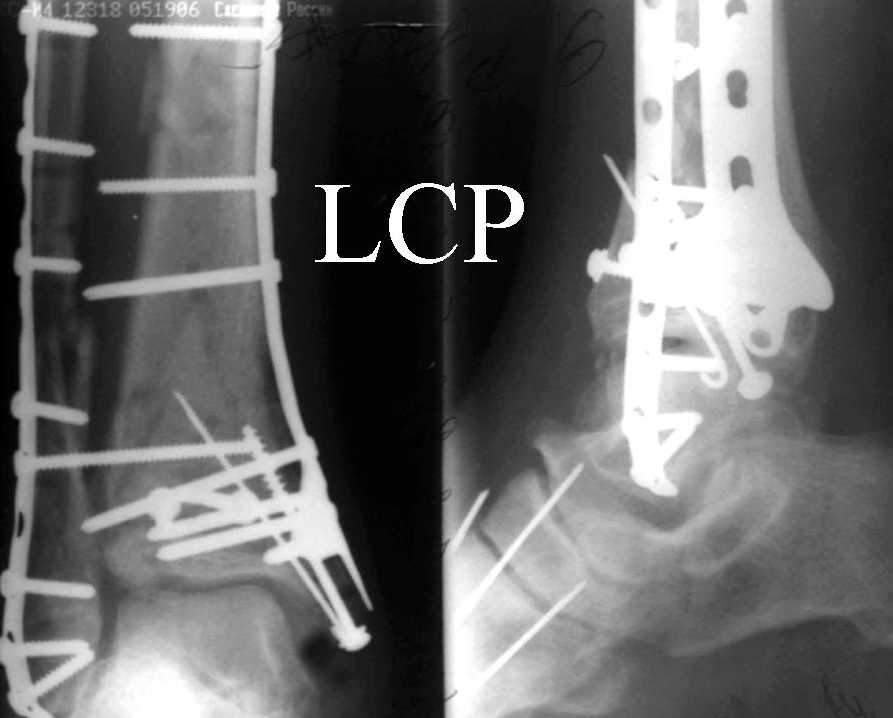

Посмотрим вроде прошло если понравится напишите расскажу как это сделать.По принципам АО кстати при поступлении сначала восстанавливают длину малоберцовой кости фиксируют пластиной 1/3 трубки потом накладывают аппарат наружной фиксации и через 7-10 дней открыто восстанавливают большеберцовую кость.С уважением Дрягин

На рентгенограммах типичный перелом пилона по типу С-3. есть опыт до 100 открытых опреаций у нас в клинике. 20 примерно в год. Принцип один -все внутрисуставные переломы нуждаются в открытой репозиции и внутренней стабильной фиксации. При поступлении КТ не надо, так как получается только нагромождение костей. Истинной картины нет. Главное восстановить длину малоберцовой кости - это ключ к успеху. При поступлении меньше всего надо думать о сосудистых расстройствах, т.к. сама операция и репозиция даже сначала частичная даёт улучшение сосудитых нарушений. Причём очень быстро. Операция в 2этапа. При поступлении доступ позади наружной лодыжки, причём обязательно. После этого репозиция малоберцовой кости и фиксация пластиной 1/3 трубки под винт 3,5. Дренаж и любой аппарат наружной фиксации. Затем после спадения отёка на 5-7-10 день аппрат снимается и дугообразный разрез спереди от медиальной лодыжки 10-12 см. Главной чтобы расстояние между 1 и вторым разрезом было не меньше 7-8 см. Тогда не будет некрозов лоскутов. Таранная кость используется как матрица на неё укладываются отломки и фиксируются пицами. Ренг-контроль. Отломки лежат все отдельно, но ничего не высыпется. При переломах С-3 всегда нужна костная пластика (из крыла). Фиксация пластиной лист клевера простой или LCP. Гипс не нужен. Дренаж до 48 часов. Операция длится 3-4 часа обязательно без жгута. Посылаю примерно такой же случай.

Принципиально все же, наверно, хорошее восстановление формы суставной поверхности. На именно внутренней фиксации тут свет клином не сошелся. Хорошо известно, что при переломах пилона широко применяются и аппараты (циркулярные или гибридные), и комбинация внешней фиксации с минимальной внутренней.